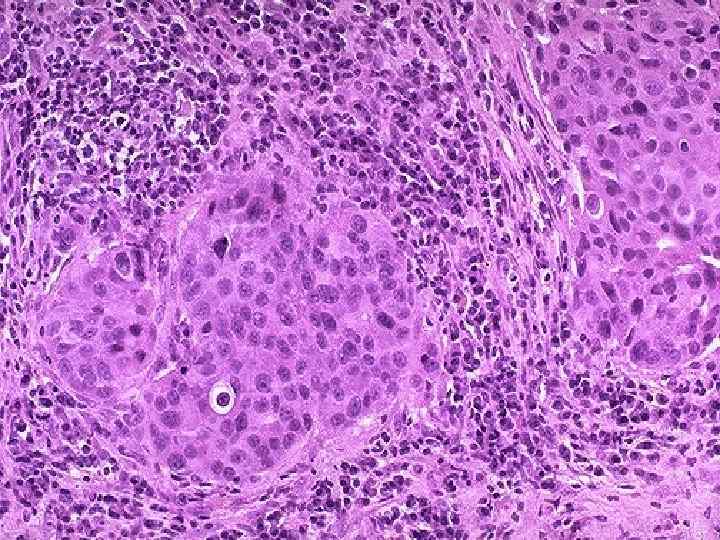

Семинома